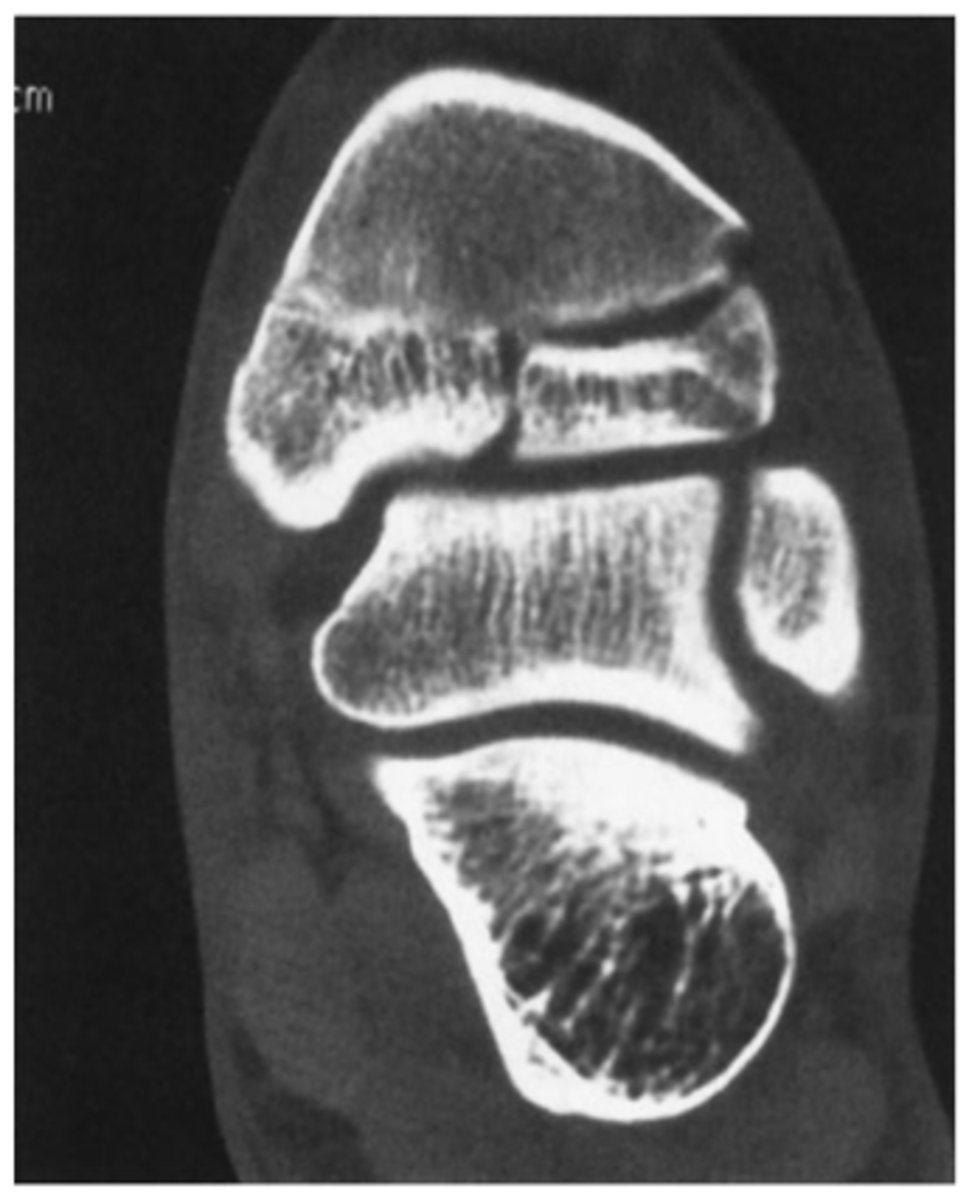

Where is the fracture here? This is the x-ray and CT

Answer

Calcaneal fracture. It is comminuted. We cant really see the degree to which it is involved on the x-ray.

CT is showing oriented fracture lines entering the posterior facet of the posterior and middle subtalar joints.

There is also a comminuted fracture of the calcenocuboid joint.

Moral of this: note how well the CT confirmed this for you